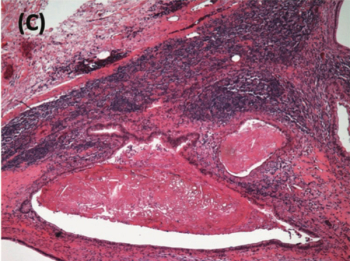

Key points: Patients with disorders of sex development (DSDs) are at an increased risk of malignant germ cell tumors (GCTs). In adulthood, the partial form of androgen insensitivity syndrome confers the greatest risk of developing malignant GCTs. Gonadoblastoma is the most common gonadal GCT arising in patients with DSDs. Despite being a benign neoplasm, it can undergo malignant transformation in up to 60% of patients with a DSD. Oncologic treatment in patients with disorders of sex development and malignant GCTs does not differ from the standard treatment for testicular GCTs. Treatment of patients with DSDs requires a multidisciplinary team, including a psychiatric, genetic, and reproductive assessment as well as the involvement of an ethics committee. An early diagnosis of DSDs is crucial to avoid the development of potentially serious complications in adulthood.